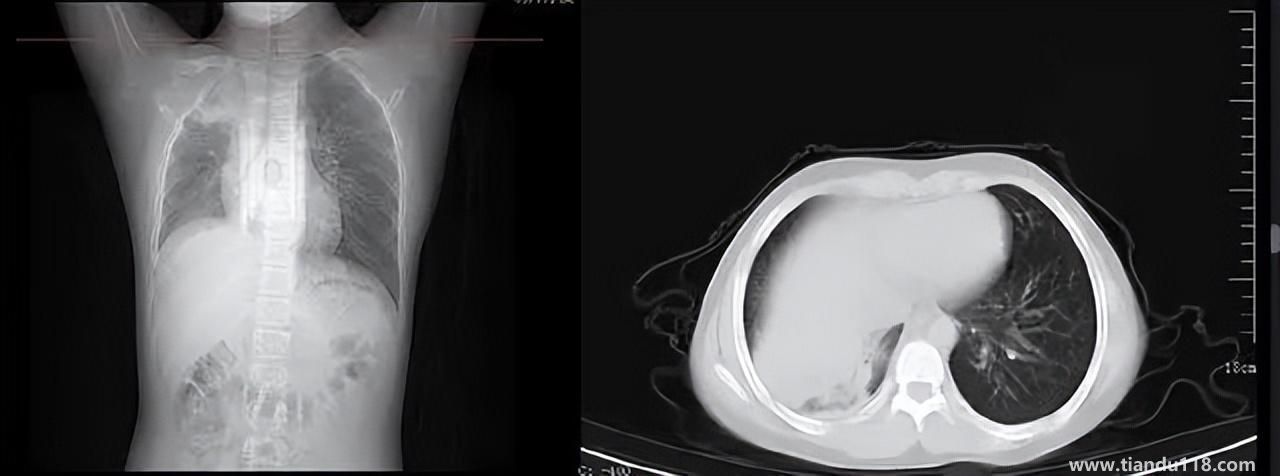

3個(gè)辦法可提前預(yù)警白肺(咋預(yù)防“白肺”) 3個(gè)辦法可提前預(yù)警白肺(咋預(yù)防“白肺”)家里有老人,擔(dān)心出現(xiàn)“大白肺”、“沉默型缺氧”等情況,具體如何應(yīng)對(duì),提前預(yù)警?近日,大象新聞接到諸多咨詢。針對(duì)這些問題,大象新聞?dòng)浾咦隽硕喾讲稍L。什么是白肺?對(duì)... 小編 2022-12-28 693

男孩咳嗽發(fā)熱在家硬扛成白肺(醫(yī)生表示以下幾種情況別硬“扛”) 男孩咳嗽發(fā)熱在家硬扛成白肺(醫(yī)生表示以下幾種情況別硬“扛”) 近日,一名12歲男孩咳嗽一周不就醫(yī),一側(cè)肺部“扛”成了“白肺”?!氨е鴥e幸心理一直在家硬‘扛’,沒想到‘扛’出這么重的?。 焙⒆蛹议L悔不... 小編 2022-12-28 939

為何有人出現(xiàn)“白肺”?專家回應(yīng)和疫苗接種無關(guān) 為何有人出現(xiàn)“白肺”?專家回應(yīng)和疫苗接種無關(guān)國務(wù)院聯(lián)防聯(lián)控機(jī)制12月27日召開新聞發(fā)布會(huì),針對(duì)有媒體提問稱,從近期公眾的反映情況看,有的新冠病毒感染者在就診過程中發(fā)現(xiàn)了肺炎或者是CT出現(xiàn)了“白肺”的現(xiàn)... 小編 2022-12-27 817

感染新冠會(huì)變白肺?醫(yī)生:有年輕病例 感染新冠會(huì)變白肺?醫(yī)生:有年輕病例感染新冠會(huì)變白肺嗎?對(duì)此,有專家表示,造成“白肺”情況有很多種,感染新冠只是一種可能。少量患者肺有滲液 ,咳嗽不會(huì)引發(fā)白肺,有年輕人病例。... 小編 2022-12-27 608